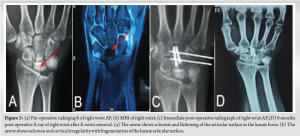

A 30-year-old female with complaints of right wrist pain for 1 year, which is insidious in onset, progressive in nature, and associated with tenderness at the radio lunate facet. A plain radiograph of the right wrist showed sclerosis and flattening of the articular surface in the lunate bone (Fig. 3A). MRI right wrist showed sclerosis, cortical irregularity with fragmentation of lunate articular surface, features suggestive of stage 3A Kienbock’s disease (Fig. 3B). Patient underwent right capitate shortening osteotomy + capitate hamate fusion + vascularized radial bone grafting (based on 4,5 extensor compartment artery) of lunate bone. Table 2 summarizes the pre-operative findings of the Quick dash score, VAS score, Grip strength of the affected and unaffected side, ROM of the affected and unaffected wrist, Youm index, and the scapholunate angle at the time of presentation, and post-operative findings on the last follow up. Both patients were put on a cast for four weeks postoperatively, and suture removal was done on post-operative day 12. Patients following the cast removal were put on a thermoplastic cockup splint. Wrist and finger mobilization exercises and grip strengthening exercises were started. The mean follow-up period was 12 years. Both patients had the right dominant hand involved. Both patients had almost complete resolution of pain and a significant reduction in the Quick DASH score. There was a significant improvement in grip strength, but some restriction of the range of movement at the wrist joint. Patients had preservation of pre-operative carpal alignment. There was no further collapse of the lunate compared to pre-operative X-rays.